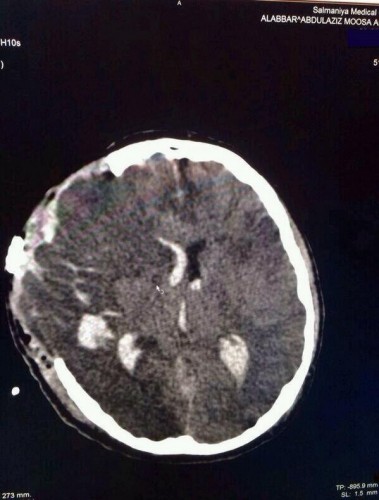

وأظهرت أشعة حديثة تلفا كبيرا في خلايا الدماغ نتيجة النزيف الحاد الذي خلفته طلقات الرصاص »الإنشطاري الشوزن«، التي قرر الأطباء أن التدخل لإزالتها من الدماغ قد يتسبب في خطر أكبر على حياته.

صورة لأشعة الشهيد عبدالعزيز العبار تظهر تلف خلايا المخ بعد اختراقها بالرصاص على يد قوات النظام البحريني |